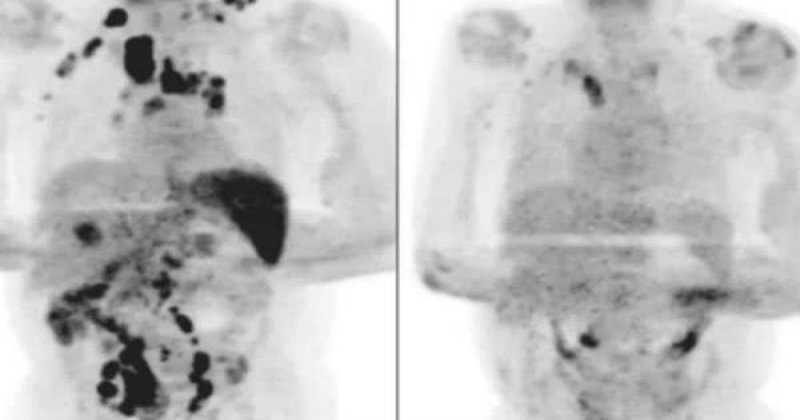

La pandemia del Covid-19 ha dejado muchos duelos en el mundo; sin embargo, a los expertos ha sorprendido un raro caso en específico, pues una persona con linfoma de Hodgkin se curó debido al nuevo coronavirus.

Este caso médico, publicado en el British Journal of Haemathology, pudo superar este tipo de cáncer pese a estar en fase 3 y tener todos los pronósticos en contra, pues su salud estaba deteriorada a sus 61 años.

Fue así que el sujeto estuvo bajo cuidados médicos y luego de 11 días de estar bajo supervisión, fue dado de alta para convalecer en su casa.

Los expertos destacaron que durante ese tiempo no se le administró ningún corticosteroide ni alguna inmunoquimioterapia, por lo que al pasar cuatro meses, se sorprendieron al ver que el linforma se habí reducido considerablemente.

La hipótesis de los expertos es que la infección del Covid-19 desencadenó una respuesta inmunitaria antitumoral.